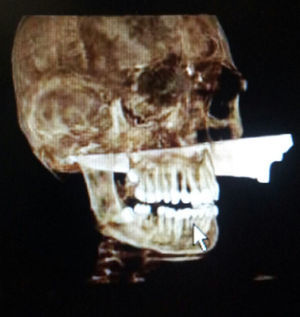

Tras comprobar condiciones de estabilidad hemodinámica se realizó un estudio radiológico (figs. 2 y 3) y se decidió intervención quirúrgica urgente por probable compromiso de la vía aérea basado en la trayectoria del arma.

Imagen de tomografía axial computarizada (TAC) donde se muestra cuerpo extraño (cuchillo) que se introduce por región maxilar izquierda atravesando paladar duro y cavidad oral. Su punta provoca una subluxación de la articulación temporomandibular y lesión parafaríngea derecha con burbujas aéreas.